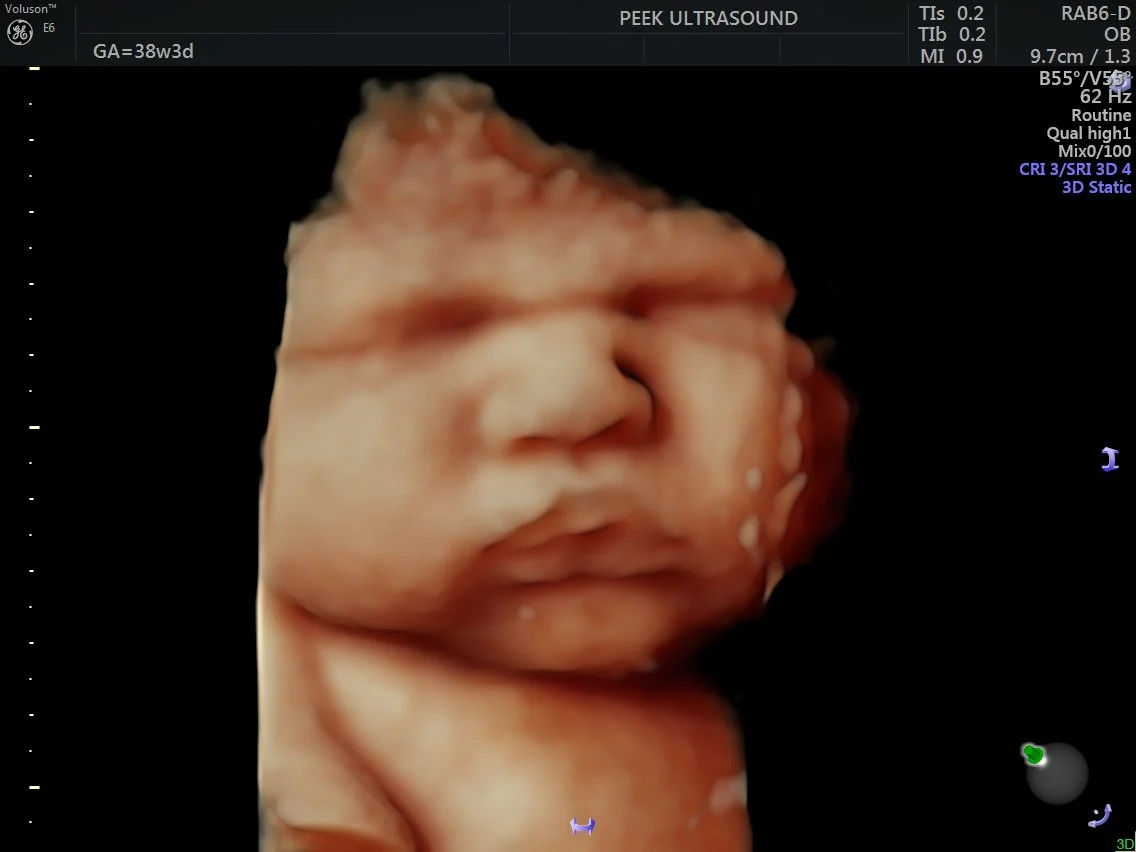

• One last peek in 3D before you meet your baby, specially designed and discounted for moms approaching the finish line!

• 15 minute 2D/3D/4D/HD scan

• 36+ weeks pregnant only

• Heartbeat measurement

• 10 black & white printed images

• 2 4×6” HD color prints

• Gender confirmation if desired

• All images/videos sent digitally via email

• Includes one (1) complimentary rescan if baby is hiding